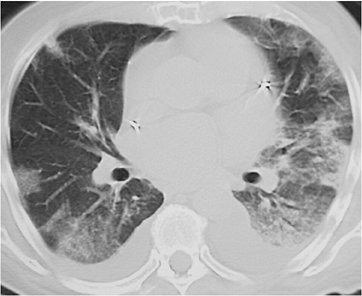

FIGURE 12-7. Chronic eosinophilic pneumonia. A: PA chest radiograph of a 30-year-old woman with several months' history of productive cough, fever, fatigue, chills, and dyspnea on exertion, treated unsuccessfully with several courses of antibiotics, shows bilateral ill-defined opacities, predominantly in the mid lungs. B: CT shows peripheral and central airspace disease. C: CT coronal reformatted image clearly shows the subpleural, peripheral distribution of disease (arrows). The patient improved rapidly with steroid treatment.